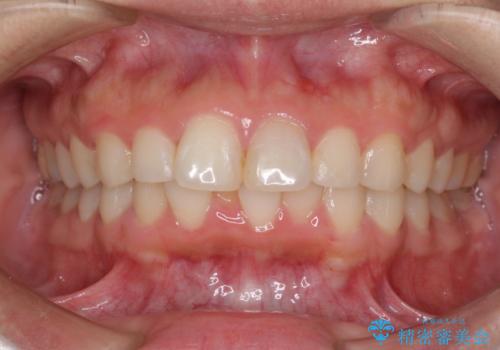

- 以前の矯正治療の後戻りを気にして来院された患者様です。

下顎前歯にデコボコがあるため、ワイヤー矯正により改善することとしました。